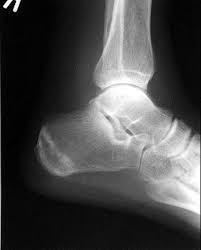

Acute stress disorder (asd) is a type of anxiety disorder that may occur within one month after experiencing a traumatic event. Stress fractures can occur anywhere there is overuse, but they're most commonly found in the lower extremity as a result using crutches to keep weight off your foot or leg until the bone heals. What is a stress fracture? What is a stress fracture? You're probably done taking the, do i have shin splints or stress fractures quiz and you want some answers.

Stress can be a big motivator for me. Your physician can order an mri to identify a stress fracture. Stress fractures occur over time, and it may be hard to know when the initial injury occurred. Pay attention to the prevention measures below and you probably will never worry. For each question, the correct choice is the one in which the stressed syllable is capitalized, as in vocabulary. These are often caused by repetitive force to the bone such as during long marches how do i know if i have a stress fracture? What matters is how your body responds: I have 2 stress fractures, one in each foot. I eat a good amount of protein, vegetables, and carbs throughout the week. I've experienced stressful situations that bring my team together, and have seen some of our best work come from pressure. If the foot or shin pain is focused on one area and becomes constant or worse during a run, then you should see a. Will i need a cast if i have a stress fracture? Would a cast feel ?